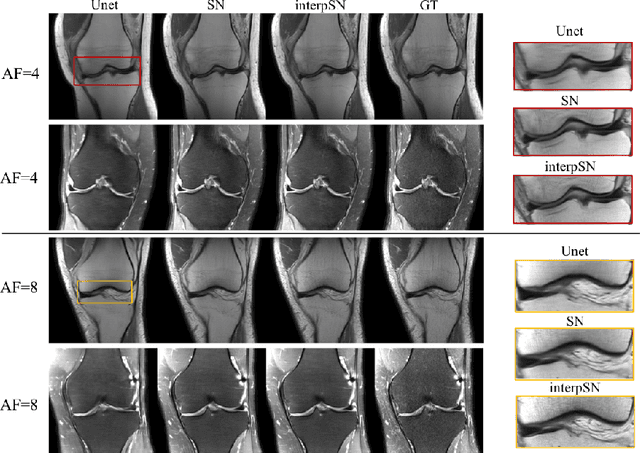

Abstract:We present a deep network interpolation strategy for accelerated parallel MR image reconstruction. In particular, we examine the network interpolation in parameter space between a source model that is formulated in an unrolled scheme with L1 and SSIM losses and its counterpart that is trained with an adversarial loss. We show that by interpolating between the two different models of the same network structure, the new interpolated network can model a trade-off between perceptual quality and fidelity.